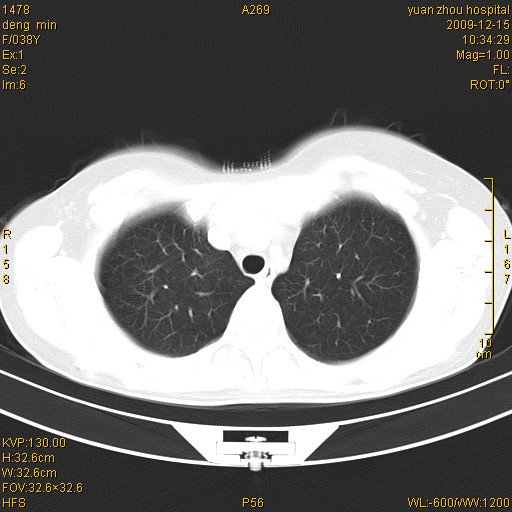

标题: CT23919:F38Y 咳嗽月余 [打印本页]

标题: CT23919:F38Y 咳嗽月余

右肺中下叶、左肺上叶舌段及左肺下叶支气管扩张合并感染。